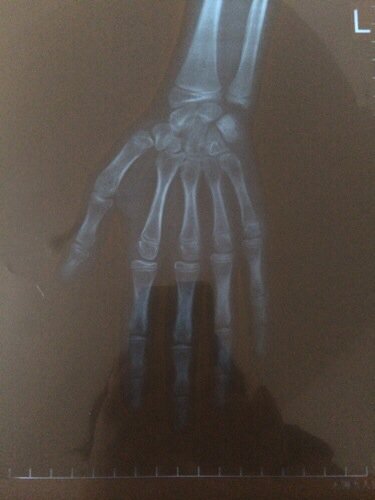

女孩来了月经还有长高的可能吗?在医院做了骨龄,有没有闭合我看不懂,请看得懂的帮我看看,看看还有没有

女孩来了月经还有长高的可能吗?在医院做了骨龄,有没有闭合我看不懂,请看得懂的帮我看看,看看还有没有长高的可能,回答好的一定采纳。         还有就是月经来了还有多少公分长的可能。

没愈合可以长个